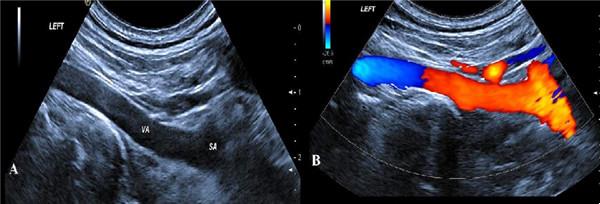

二、开的是“彩超”,为什么是黑白的?

彩超的“彩”指彩色多普勒,并非指屏幕是彩色的,所有的超声都是基于二维超声,“彩色”是反映的血流情况,咱们医院的四维彩超仪器可都是国际一流设备GE及Philips品牌。